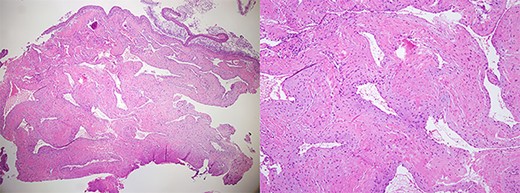

A 60-year-old woman visited an otolaryngologic clinic due to itching and intermittent pain in the right ear that persisted for a month. Otoscopic examination showed a red tumor with a lobulated margin in the right EAC (Fig. 1A). She had a medical history of chronic renal failure, with no previous ear trauma or surgery. She was lost to follow-up for further evaluation after the first visit; however, she was re-visiting after 3 years. The patient did not report any symptoms, such as otalgia, fullness of the ears, dizziness, otorrhea, pulsatile tinnitus or hearing loss. The tumor had increased in size and had grown from a flat tumor into a round, bulging tumor close to the tympanic membrane (Fig. 1B). High-resolution non-contrast computed tomography (CT) imaging of the temporal bone revealed an 8.1 × 5.8-mm soft tissue mass in the posteroinferior wall of the right external ear (Fig. 2). The tumor was 3.1 to 4.0 mm away from the inferior annulus of the tympanic membrane. There was no evidence of bone erosion and the tympanic membrane and the middle ear appeared normal. The patient underwent endoscopic resection of the tumor via a transcanal endoscopic approach (Fig. 3). The inferior EAC mass was excised in bloc by elevating the skin in continuity with the lesion. The healthy surrounding skin 2 mm from the tumor margin was also removed. Bleeding was controlled by bipolar cautery. No significant bleeding was encountered. The skin defect in the ear canal was reconstructed by tragal perichondrium. Pathologic examination of the sample revealed the diagnostic features of cavernous hemangioma, with vascular spaces lined by a single layer of flat endothelial cells without atypia or mitosis (Fig. 4). The patient healed well after surgery, with no sign of recurrence after 10 months.

Histopathological image showing features of cavernous hemangioma (H&E stain, ×40, ×100).